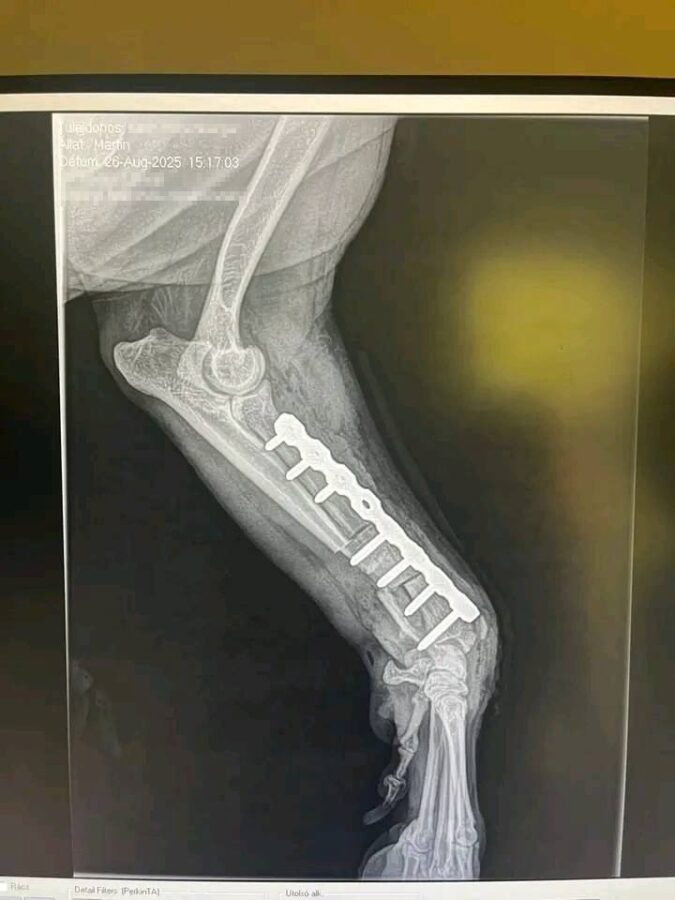

Die tierärztlichen Dokumente und Rechnungen nennen den Namen Karin Hohenberger.

In ihrem öffentlichen Facebook- oder Instagram-Profil finden sich zahlreiche Posts über ihren Rottweiler „Martin“ – unter anderem zu seiner OP und Genesung:

➡️ Das spricht eindeutig dafür, dass Karin Hohenberger die rechtmäßige Halterin ist, die Martin durch die medizinische Versorgung begleitet und öffentlich dokumentiert hat.

Die Bilder (von mir anonymisiert)

- Der Hund ist kein Dobermann, sondern eindeutig ein Rottweiler (laut Unterlagen und äußerlich).

| Rasse | Dobermann (falsch) | Rottweiler (nach Dokumenten & Erscheinung) |

- Der Hund auf den Bildern heißt Martin, ist ein Rottweiler und wird von Karin Hohenberger versorgt.